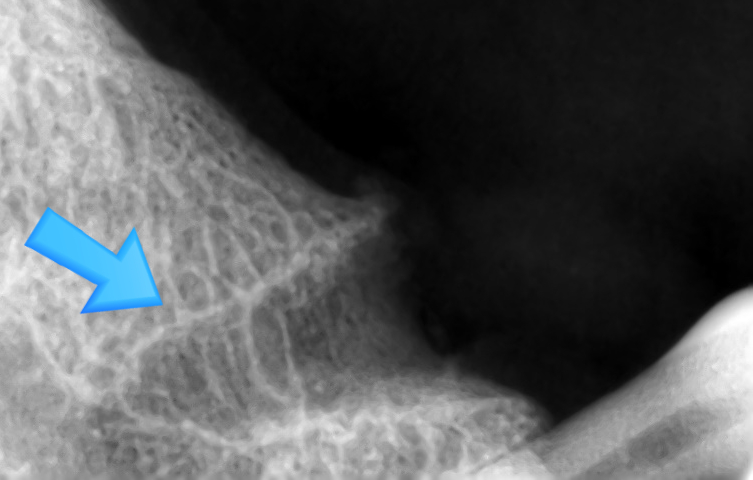

표시해드릴게요 ↓

일반 분들은 이 선이 치아 신경인지 치조골인지, 치아주변인대인지

구별하기 쉽지 않을 것입니다.